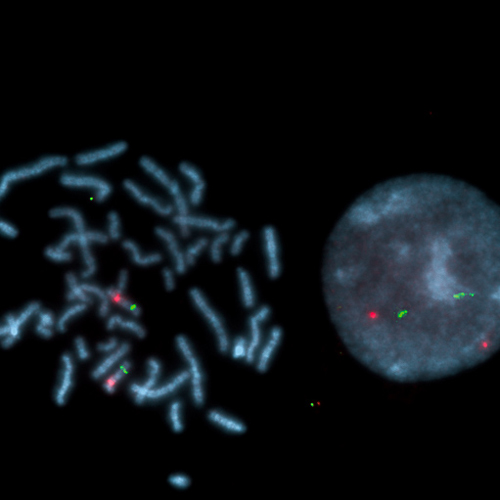

Prader-Willi SNRPN (15q11) / PML (15q24) probe hybridized to a normal interphase/metaphase (2R2G).

Prader-Willi Syndrome (PWS) is a clinically distinct disorder including diminished fetal activity, obesity, hypotonia, mental retardation, short stature, hypogonadotropic hypogonadism, strabismus, and small hands and feet. Approximately 70% of cases of PWS arise from paternal deletion of the 15q11-q13 region including the gene SNRPN (small nuclear ribonucleoprotein polypeptide N). The PWS SNRPN region probe is optimized to detect copy numbers of the SNRPN gene region at 15q11. The PML (promyelocytic leukemia) gene specific FISH probe at 15q24 is included as control probe.